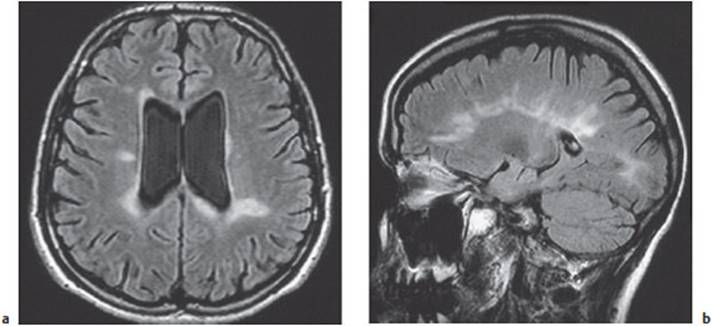

Neuroimaging studies, particularly MRI, typically reveal abnormal white matter signal in the periventricular regions and the corpus callosum. Active MS plaques take up contrast medium Fig. 8.3.

Fig. 8.3 MRI of the brain in multiple sclerosis. a Asymmetrically scattered foci of abnormal signal, affecting only the white matter, are seen in the periventricular regions and at the anterior and posterior ends of the lateral ventricles. There is mild internal hydrocephalus. b There are typical signal abnormalities in the corpus callosum, extending into the white matter of the hemispheres.